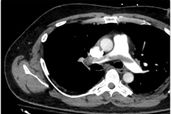

In the meantime, while we are awaiting clinical trial outcomes,  we want to assess any patient with proximal pulmonary emboli who demonstrate biochemical and radiographic evidence of RV strain with any one of the clinical parameters outlined in our call criteria.  Consequently, the full range of medical and interventional therapies can be discussed by the multidisciplinary pulmonary embolism response team (PERT)  and these patients will be monitored in the Intensive Care Unit.